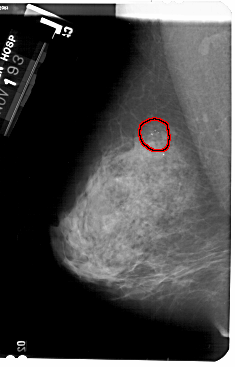

FILE: A_1732_1.LEFT_MLO.OVERLAY

TOTAL_ABNORMALITIES 1

ABNORMALITY 1

LESION_TYPE CALCIFICATION TYPE AMORPHOUS DISTRIBUTION CLUSTERED

ASSESSMENT 2

SUBTLETY 4

PATHOLOGY BENIGN

TOTAL_OUTLINES 1

BOUNDARY